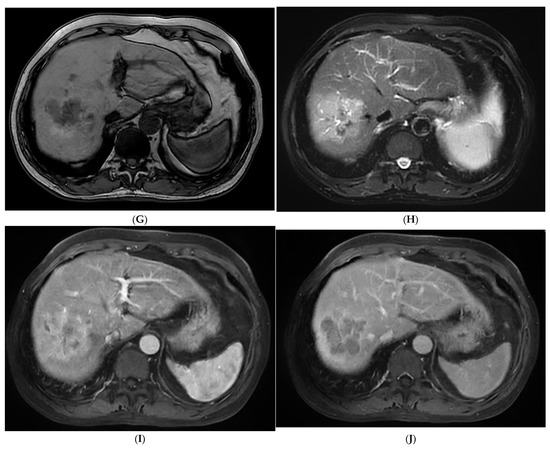

Figure 1.

The contrast-enhanced ultrasound (CEUS) and contrast-enhanced magnetic resonance imaging (CEMRI) of steatohepatitic hepatocellular carcinoma (SH-HCC). A heterogeneous hyperechoic le-sion was detected in the right lobe of the liver (A). Short linear blood flow signals were seen in the peripheral of mass (B). As seen via CEUS, the hepatic nodule did not show rim, peripheral dis-continuous or heterogeneous hyperenhancement in the early arterial phase (C). During the portal venous phase, it was continuous iso-enhancement (D). It exhibited mild washout in the late phase (E). The hepatic lesion was heterogeneous hypointense on T1WI (F). A signal drop in the T1WI opposed-phase was observed (G). It was marked as hyperintense on unenhanced T2WI (H). After injection of contrast agent, the hepatic lesion showed non-rim hyperenhancement in the arterial phase (I). It became hypo-intensity during the late phase (J).

3.3. CEMRI Features

As shown in Table 3, SH-HCCs mainly showed hypo-intensity on T1WI and hyperintensity on T2WI, and there were no significant differences between the two groups (p > 0.05). However, there was a signal drop in the T1WI opposed-phase which was observed in 84.6% of SH-HCCs, which was much higher than for the non-SH-HCCs (p = 0.000). As seen via a contrast-enhanced scan, most SH-HCCs and non-SH-HCCs exhibited heterogeneous hyperenhancement in the arterial phase (80.8% versus 69.2%, p = 0.337). During the delayed phase, 76.9% (20/26) of SH-HCCs and 88.5% (23/26) of non-SH-HCCs exhibited hypo-enhancement (p = 0.264). As a result, SH-HCCs and non-SH-HCCs were mostly classified into LR-4 or LR-5. Notably, diffuse fat in mass was detected in 57.7% (15/26) SH-HCC lesions, which was significantly higher than for non-SH-HCCs (p < 0.001). Hemorrhage and necrosis in mass were of similar frequency in the two groups (p = 0.350, p = 0.703, respectively). The contrast-enhanced images of SH-HCC are shown in Figure 1, and images of non-SH-HCC are displayed in Figure 2.

In the present study, the MRI characteristics of SH-HCCs were also fully analyzed. The most notable result was that a signal drop was observed in 84.6% of SH-HCCs in the T1WI opposed-phase compared with the in-phase. In addition, a diffuse fat change in mass was seen in 57.7% of SH-HCCs. Our results were in line with Inui et al. [13]. As seen via contrast-enhanced scan, even though 88.5% of SH-HCCs showed hyperintensity in the arterial phase, the remaining 7.7% of these lesions exhibited hypo-intensity. Hypovascular enhancement is characteristic of the progressed HCCs but not for early, fatty degeneration or well-differentiated HCCs [29,38]. That is to say, the fact that they are fat-containing coincides with the presence of enhancement intensity during the arterial phase, and the SH-HCCs with a dominant fat component show less conspicuous enhancement [13,39]. During the portal venous and delayed phase, 76.9% of SH-HCCs started to show hypo-intensity. As a result, 80.7% of SH-HCCs were classified into LR-4 or LR-5. In a word, SH-HCCs presented the characteristics of fat degeneration as well as enhancement performance of standard HCCs.